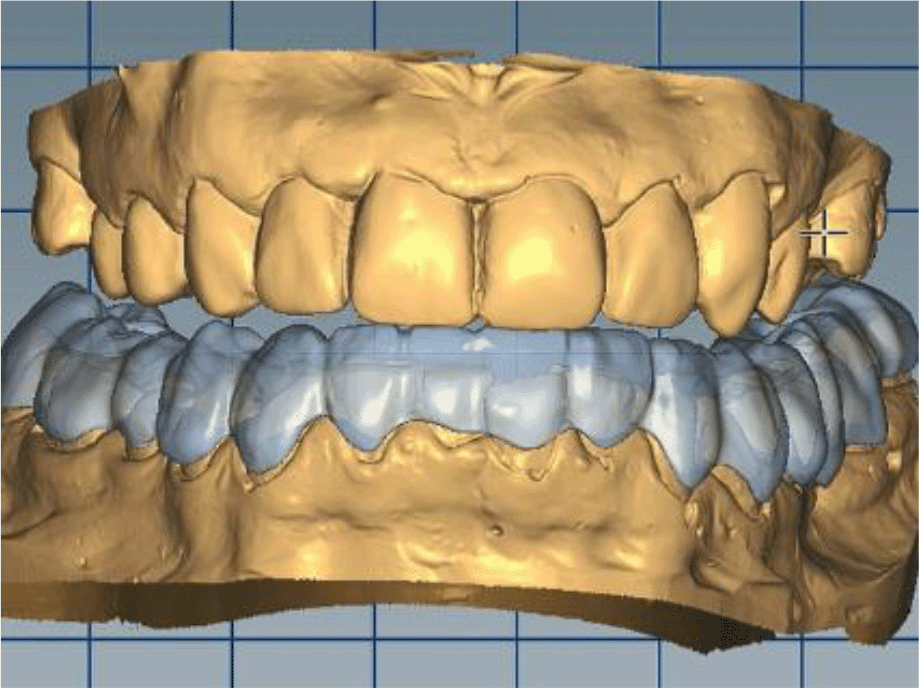

The cast gypsum models were scanned with a laboratory scanner and the obtained digital models were subjected to additional processing. Briefly, transfer of the morphological planning for the upper dentition (crown strategy) and for the lower dentition (digital wax up strategy, pontics) was performed (Figures 9 and 10).

26dd931c-41d3-478d-bec1-8cb211d0a4b8_figure9.gif

Figure 9. Clinical situation after upper preparation with increased VDO.

26dd931c-41d3-478d-bec1-8cb211d0a4b8_figure10.gif

Figure 10. Digital design on both jaws.